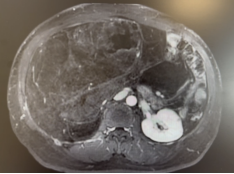

56岁男性患者,因间断上腹不适4个月,检查发现腹膜后肿瘤2周。腹部CT及核磁提示腹膜后巨大脂肪肉瘤,直径约35cm。

我们为患者实施全麻下开放腹膜后肿瘤切除术。术中可见肿瘤挤压十二指肠、胰头、肠系膜血管、下腔静脉和腹主动脉,但未侵犯结肠、肠系膜血管等组织器官,且包膜完整。手术团队仔细游离,完整切除腹膜后肿瘤,剔除腹膜后脂肪。历时2个小时完成,术中出血约100ml。